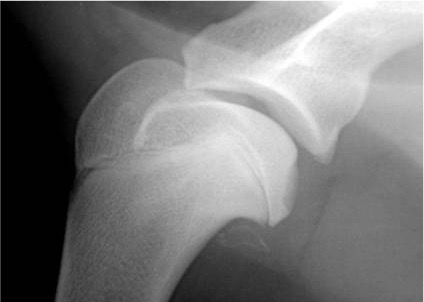

Bildgebende Verfahren – Klarheit schaffen, um gezielt zu handeln

Die bildgebenden Verfahren bieten uns im wahrsten Sinne des Wortes tiefere Einblicke, die für eine fundierte Diagnose und eine gezielte Therapieplanung entscheidend sind.

Röntgenaufnahmen können Veränderungen des Knochens und arthrotische Veränderungen des Gelenks sichtbar machen.Die Computertomografie (CT) kann darüberhinaus ein detailliertes und dreidimensionales Bild der Knochenstrukturen liefern.